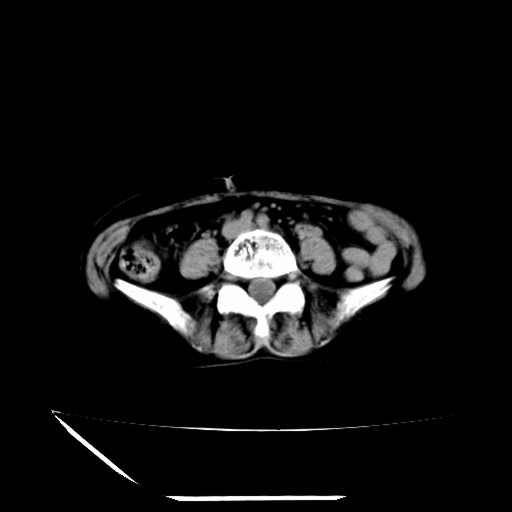

标题: CT16840:女-63岁,下腹部疼痛, [打印本页]

标题: CT16840:女-63岁,下腹部疼痛,

本人诊断是右肾周围炎,阑尾炎,盆腔少许积液!

诊断右肾周围炎是因为我图像没有发完,诊断阑尾炎是因为相当于阑尾区连续两个层面可以看到增粗的阑尾显影。

支持阑尾炎!局部腹膜增厚,脂肪密度增高。应该手术治疗。

考虑阑尾炎可能性

支持 阑尾炎,盆腔少量积液。